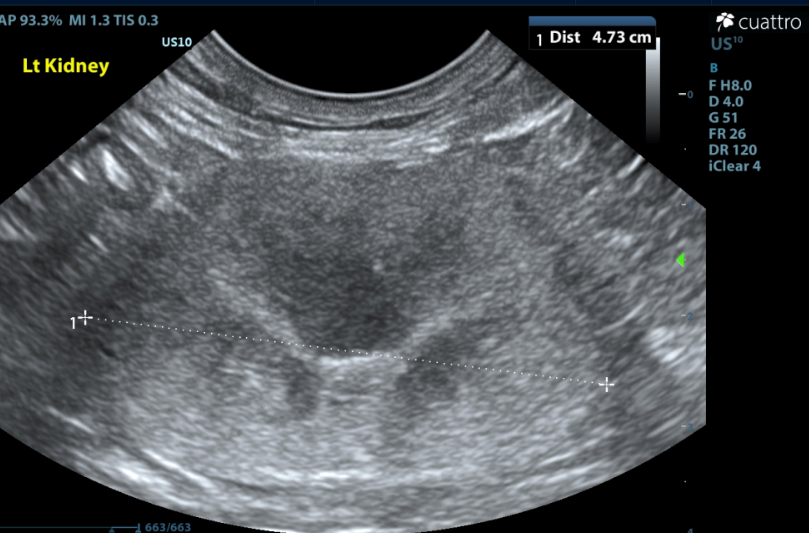

Kidneys ---Both kidneys have borderline to enlarged size (Lt/Rt =4.7 /4.1cm ) and normal shape with coarse moderately hyperechoic renal cortices which are disproportionately large. There is moderate loss of the corticomedullary junction distinction. No pyelectasia seen.

(normal renal size 3.2cm to 4.2cm; Renal Size in Cats, JAVMA, July 2005, Vo